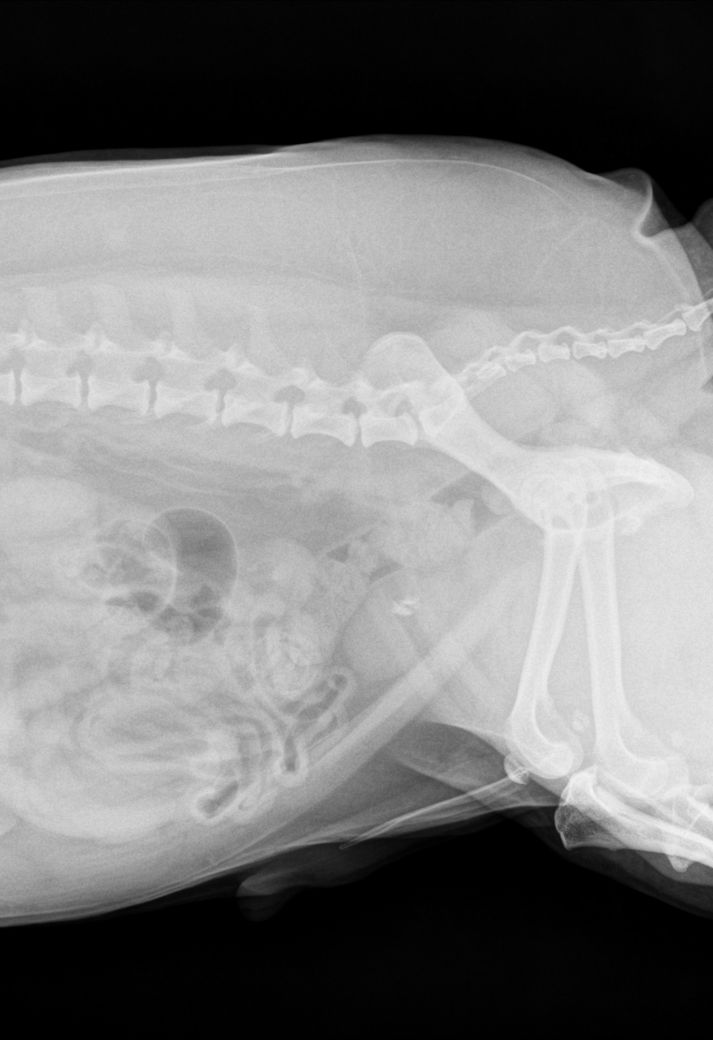

비숑 방광결석 수술 꼭 필요할까요??

방광결석으로 문의드려요.

사이즈는 사진과 같으며 2개정도라 하셨어요